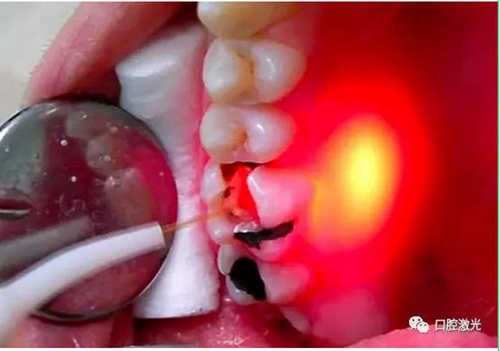

根管消毒徹底去除根管內(nèi)的感染是保證根管治療效果的關(guān)鍵步驟之一,由于根管結(jié)構(gòu)復(fù)雜,利用激光的熱效應(yīng)不僅可以進(jìn)行根管消毒,而且還可以促進(jìn)根尖周組織愈合,是目前根管治療中一種新型有效的消毒方式。

半導(dǎo)體激光根管治療臨床照片